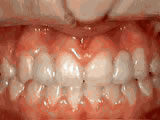

Open bite - Front teeth don't touch

Patient sucked her thumb as a young child. She started treatment at age 13. She had braces and a special appliance — called a crib — to retrain the tongue, for 28 months. Now she can bite the lettuce out of a sandwich.